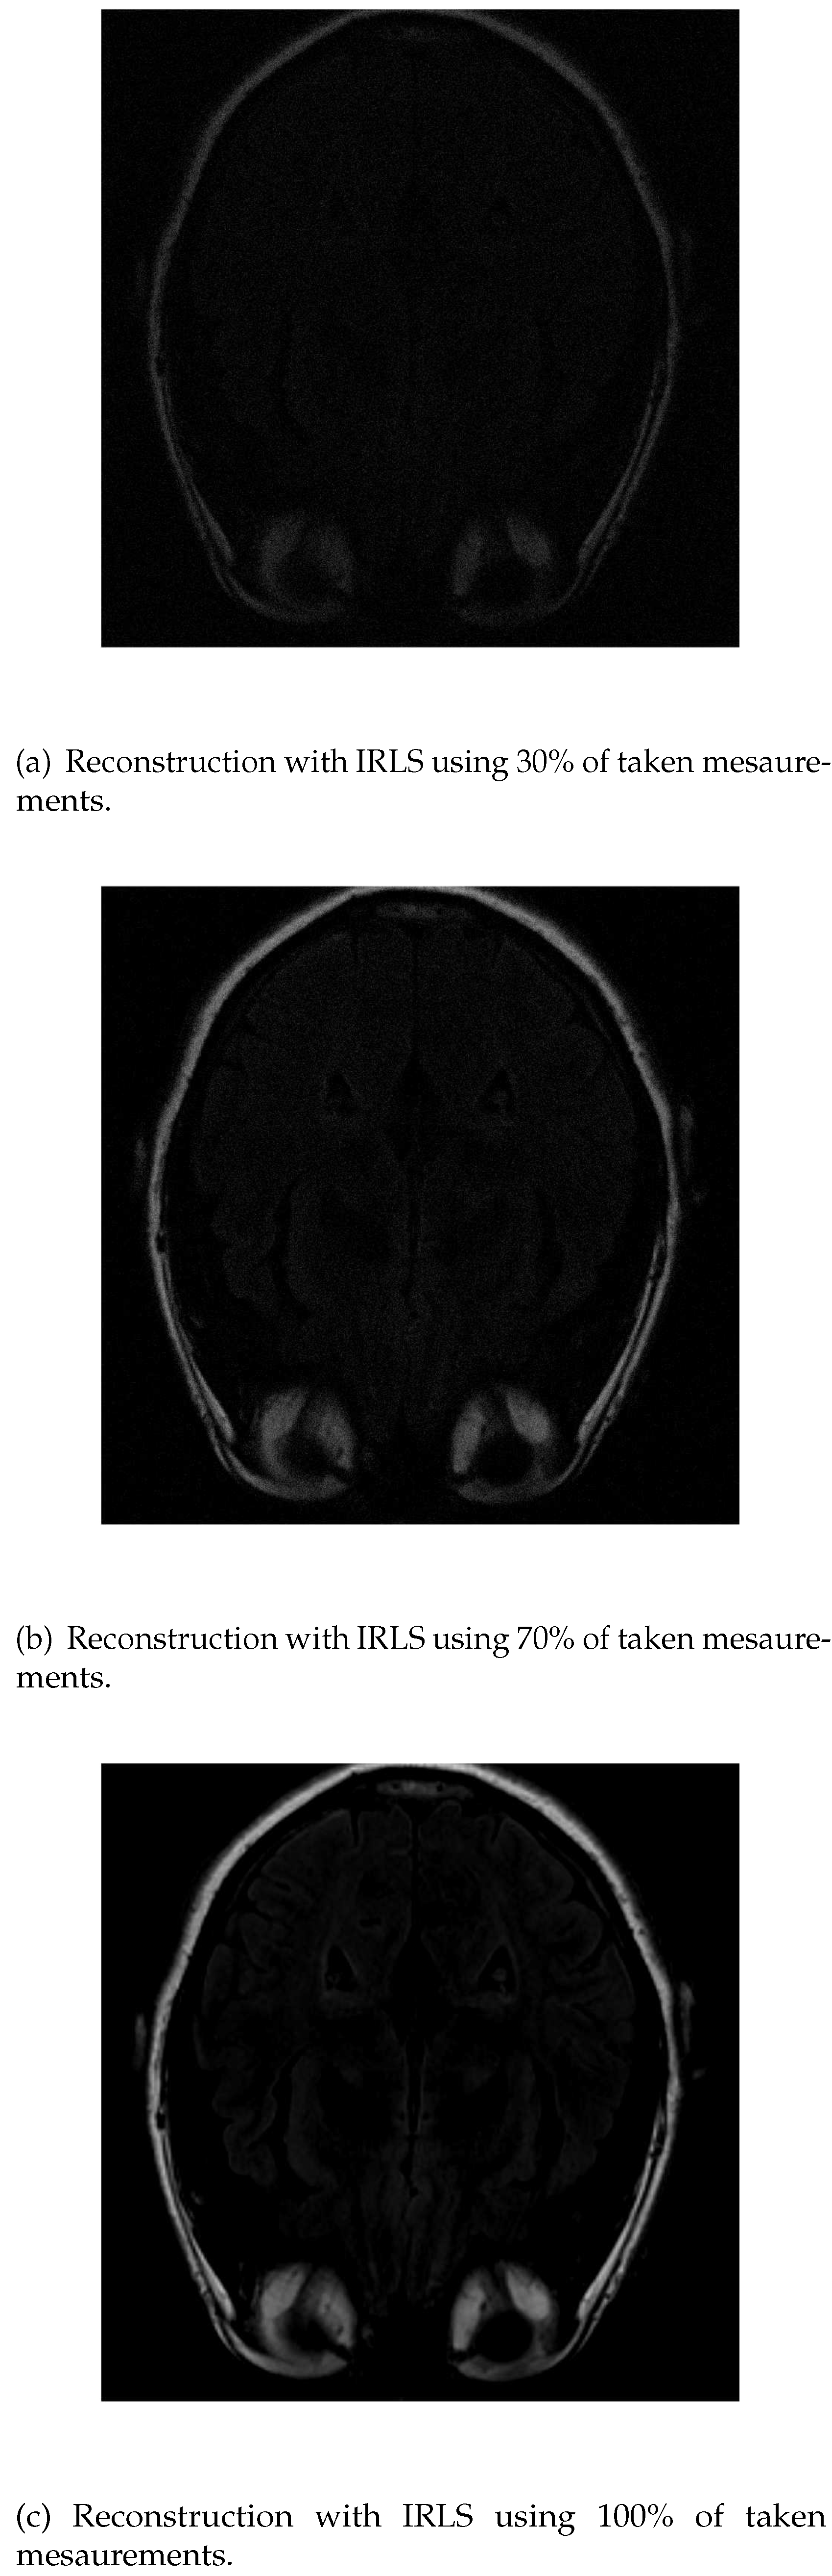

In the reconstruction by IRLS, only the outline of the head and orbits are detected in the first measurements, while the white matter is not distinguishable (Figure 5a). When 70% of the data is available (Figure 5b), the white matter can be distinguished, although it has little intensity. Also, the intensity of the orbits increases and the effect of the artifact starts to be noticed. If the algorithm is run with all the available data (Figure 5c), the resolution at the edges increases, but the intensity of the white matter signal is lost, which makes its identification more difficult.

Figure 5. Reconstruction of the image in Figure 3 using IRLS with 30 % (a), 70 % (b) and 100 % (c) of taken measurements.